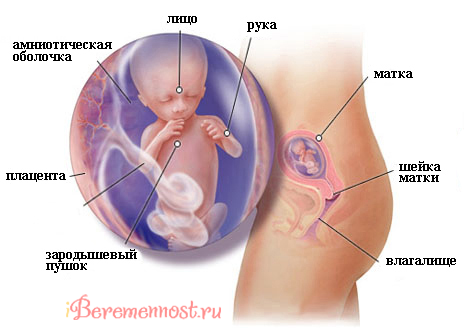

До початку 14 тижні ризик викидня буде мінімальний, живіт турбувати не буде. Плід (це можна побачити на УЗД) знаходиться під захистом плаценти, тому в цей період, якщо знадобиться, ви зможете приймати і ліки, які вам пропише лікар. І банальна застуда тепер не зможе привести до небезпечних наслідків для плода.

До початку 14 тижні ви вже зможете самостійно намацати «вагітну» матку, яка росте вгору, адже зараз вона вже досягла області, що розташовується нижче пупка приблизно на 10 см. Особливо добре буде видно підростаючий живіт, якщо в момент дослідження лягти на кушетку.

До цього терміну розмір органу відчутно збільшився, так що він «наповнив» собою тазостегнову область, «притиснувши» кишечник, і почав рости вгору, туди, де розташовується очеревина. На фото, зроблених під час УЗД, чітко видно, як при подальшому зростанні матка починає сильніше тиснути на сусідні органи. Так що скоро «дістанеться» і легким - в результаті, регулярно виникатиме відчуття, що вам не вистачає повітря.

Отже, починається 14 тиждень - малюк важить близько 20 гр, а його довжина наближається до позначки 80 мм. На фото видно, що дитина зараз не більше звичайного персика, живіт з таким «фруктом» всередині поки ще малий.

Судячи з фото плода, ваш живіт став притулком не просто суті, віддалено нагадує людину, там живе справжнісінький чоловічок. На першому плановому УЗД, яке вам належить пройти на цьому тижні, ви переконаєтеся в цьому особисто. Звичайно, голову дитини з вже оформленим личком детально розглянути ви не зможете, зате з'ясувати підлогу на цьому тижні вже можливо.

Як правило, перше УЗД проводять або на терміні в 13 тижнів, або трохи раніше. УЗД, зроблене в цей час, дозволить вам побачити дитину (або дітей) і його руху, дасть уявлення про розміри плоду, стан плаценти і матки. Важливо, що перше дослідження дозволить досить точно визначити термін появи малюка на світ.